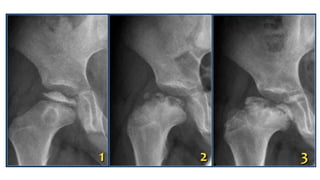

Choi's classification

Type IA: No residual

deformity

Type IB: mild coxa

magna. It needs no

reconstruction.

Type IIA: coxa brevia

with deformed head

TypeIIB: asymmetric

premature closure of

proximal femoral

physis

Type IIIA: Slipping at

femoral neck with

severe

anteversion/retrovers

ion

Type IIIB:

pseudoarthrosis -

realignment surgery

for proximal femur or

bone grafting.

Type IVA: Destruction of

the head and neck of

femur with the presence

of remnant of medial

base of neck.

Type IVB:

Complete loss of

femoral head &

neck